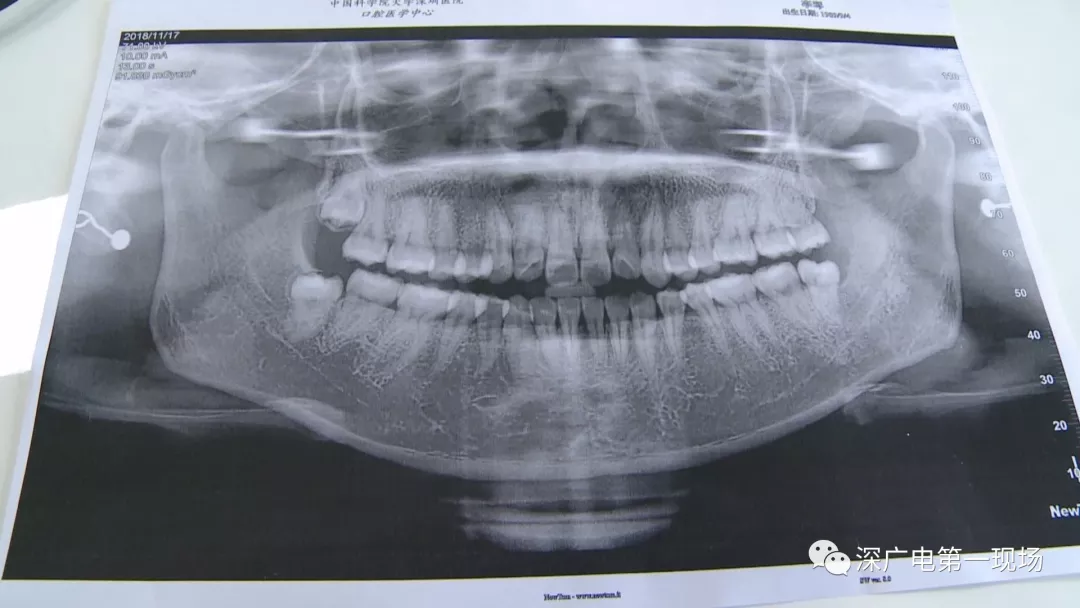

中国科学院大学深圳医院口腔科主任贾岳介绍,对于不同患者的牙齿,它的治疗方法都不一样,所以不同牙齿,医院收费的标准也各不相同。牙齿的治疗方案,都是根据患者牙齿具体情况来制定,然后再去收费,同时也会参考病人实际情况来做不同的治疗项目。